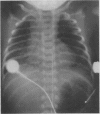

A case is reported of fulminant early-onset group B streptococcal septicemia and delayed-onset congenital right-sided diaphragmatic hernia in a neonate. The latter condition should be considered when early-onset group B streptococcal disease is followed by increasing respiratory distress, right-sided pleural effusion and partial or complete opacification of the right side of the thorax.